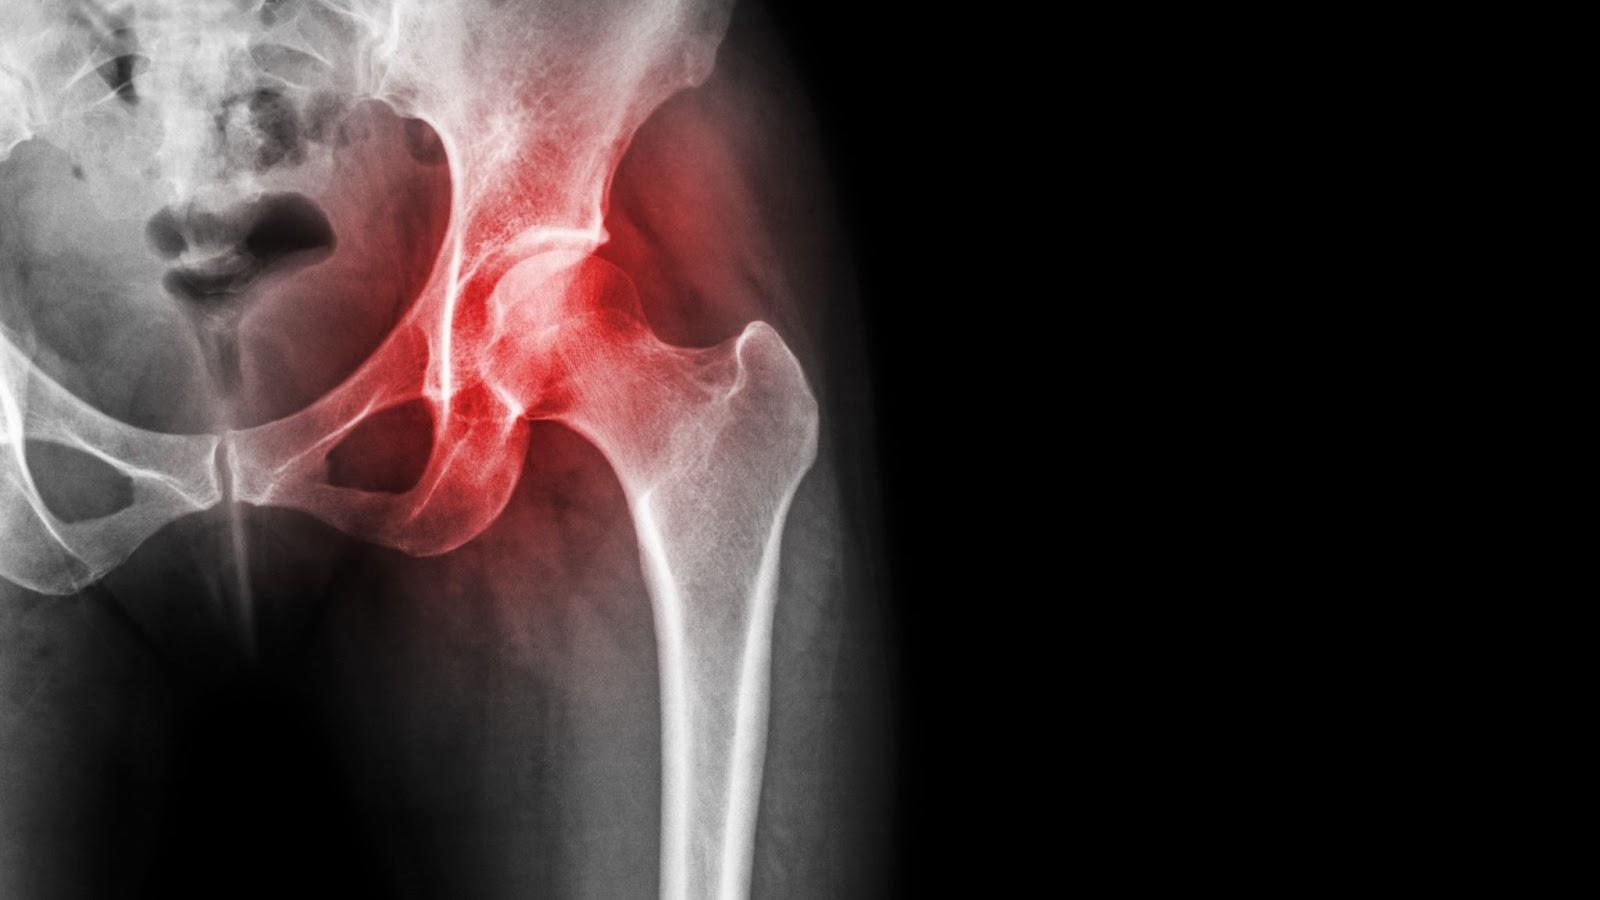

A hip labral tear refers to damage to the labrum, a ring of cartilage that lines the rim of the hip socket (acetabulum).

This cartilage acts as a cushion and stabiliser, helping to seal the joint and support smooth, fluid movement between the ball of the thigh bone (femoral head) and the socket.

When the labrum is torn, either due to trauma, repetitive stress, or structural abnormalities, it can cause pain, a clicking sensation, stiffness, and instability in the hip. In some cases, people may experience discomfort only during certain movements such as twisting, pivoting, or prolonged sitting, making the condition difficult to identify without proper evaluation.

Labral tears are increasingly recognised in both active individuals and those with underlying anatomical variations like femoroacetabular impingement (FAI). Left untreated, they may contribute to joint degeneration and the early onset of osteoarthritis in the hip.